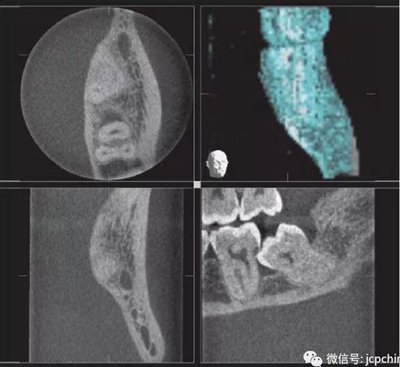

(2)射線硬化偽影

當(dāng)投射線的低能量光子被大量過(guò)濾時(shí)(如口腔銀汞),使透射過(guò)的剩余光子平均能量非常高,當(dāng)反投射時(shí),就會(huì)出現(xiàn)條狀偽影。由于口腔修復(fù)材料的阻射性質(zhì),因而射線硬化偽影非常常見(jiàn)。

(a)根尖片。

(b)CBCT矢狀面。

同一解剖位置顯示出的廣泛射線硬化偽影,使CBCT分辨金屬邊緣變得困難。CBCT圖像中27牙的近中壁缺損可能為齲損(紅色箭頭),而根尖片(黃色箭頭)卻顯示正常。